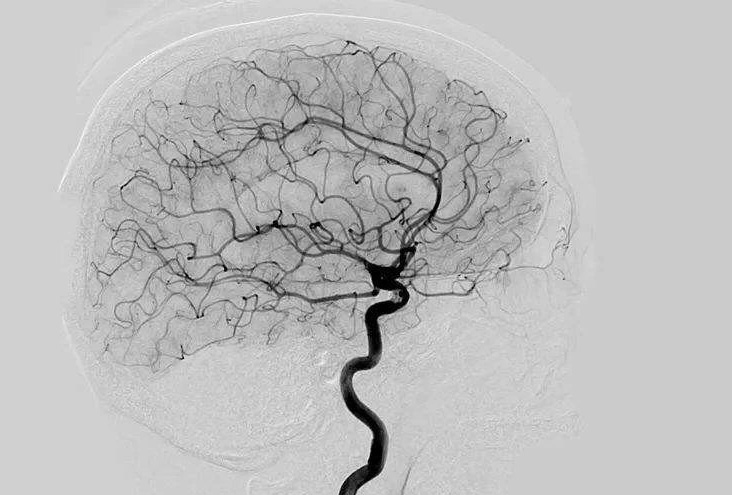

Digital Subtraction Angiography 血管造影機(jī)又稱數(shù)字減影血管造影機(jī),是通過電子計(jì)算機(jī)進(jìn)行輔助成像的血管造影方法,應(yīng)用計(jì)算機(jī)程序進(jìn)行兩次成像完成的。在注人造影劑之前,第一次成像工作,圖像轉(zhuǎn)成數(shù)字信號(hào)儲(chǔ)存,注人造影劑后,再次成像并轉(zhuǎn)換成數(shù)字信號(hào),兩次數(shù)字相減,消除相同的信號(hào),得到只有造影劑的血管圖像。臨床主要應(yīng)用于冠心病、心律失常、瓣膜病和先天性心臟病的診斷和治療。